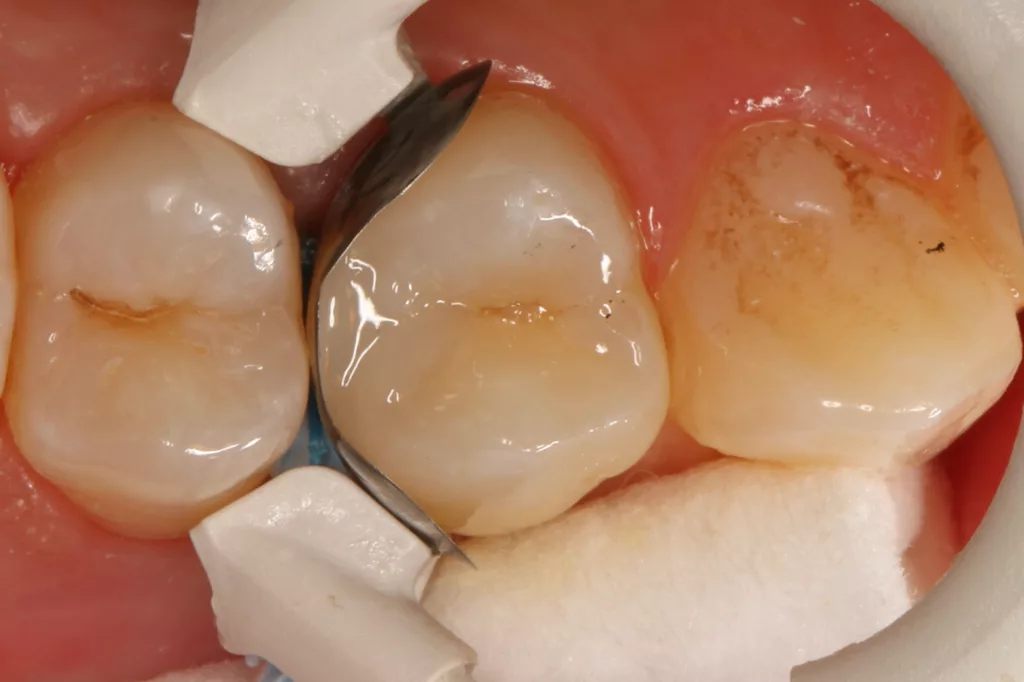

Die 26 Jahre alte Patientin störte sich an der approximalen Lücke zwischen den Zähnen 14 und 15, da sich hier ständig Speisereste impaktierten. Bei der klinischen Inspektion fiel die Initialkaries distal an Zahn 14 auf (Abb. 7). Die Patientin wurde dahingehend beraten, den Spalt mit einer minimalinvasiven Kompositrestauration zu versorgen – bei zeitgleicher Exkavation der Karies an Zahn 14. Nach Exkavation und Präparation des Defektes (der sich als deutlich ausgeprägter präsentierte als anfangs angenommen) erfolgte identisch zu Fall 2 die Ausformung der Kavität mit einer Teilmatrize (Danville ultra thin flex), einem Kunststoffkeilchen (G-Wedge) und der Separation mit einem NiTin-Prämolaren-Spannring (re-invent, Abb. 8).

Teilmatrizensysteme stellen heutzutage die erste Wahl in der Gestaltung anatomischer Kontaktflächen dar [22]: Sie garantieren korrekte anatomische Formen, straffe Approximalkontakte und belastungsoptimiert ausgeformte Randleisten [74–76]. Nach der adhäsiven Vorbehandlung (G2 Universal, GC, total etch) wurde der Defekt identisch zum vorherigen Fall mit dem niedrigviskösen Visalys Bulkflow in einem Zug aufgefüllt und mit der Sondenspitze ausmodelliert (Abb. 9). Die Aushärtung (Elipar Deep Cure) erfolgte erneut standardisiert für jeweils 20 Sek.: einmal okklusal zentral nach Einbringen des Bulkflow-Materials und je einmal als Nachhärtung nach Abnahme der Matrizen-Verschalung aus bukkaler und erneut okklusaler Richtung mit genau auf der Randleiste positioniertem Lichtgerät. So wird mit Sicherheit eine suffiziente Aushärtung des 4 mm tiefen Defektes gewährleistet.

Die Abbildung 10 zeigt das Behandlungsergebnis unmittelbar nach Ausarbeitung und Politur (Diacomp Plus Twist, EVE), die Abbildung 11 bei einer weiteren Kontrolle nach sechs Monaten. In diesem Kontrolltermin wurden dann im routinemäßigen, zwei- bis dreijährigen Intervall Bissflügelröntgenaufnahmen zur Kariesdiagnostik angefertigt. Auf der Röntgenaufnahme zeigt sich die neue Visalys-Bulk-Flow-Restauration als randdicht, anatomisch korrekt geformt und ausreichend röntgenopak (Abb. 12). Die Schmelzläsion mesial an den Zähnen 15 und 16 erschien nicht therapiebedürftig, da die Oberfläche intakt war, wohl aber die versteckte Dentinläsion distal an dem Zahn 15. Der Defekt wurde in einem weiteren Termin identisch mit denselben Materialkombinationen und identischem Polymerisationsprotokoll versorgt (Abb. 13 bis 15).